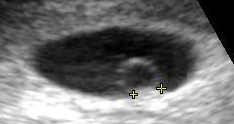

The yolk sac is the first element seen within the gestational sac during pregnancy, usually at 3 days gestation.